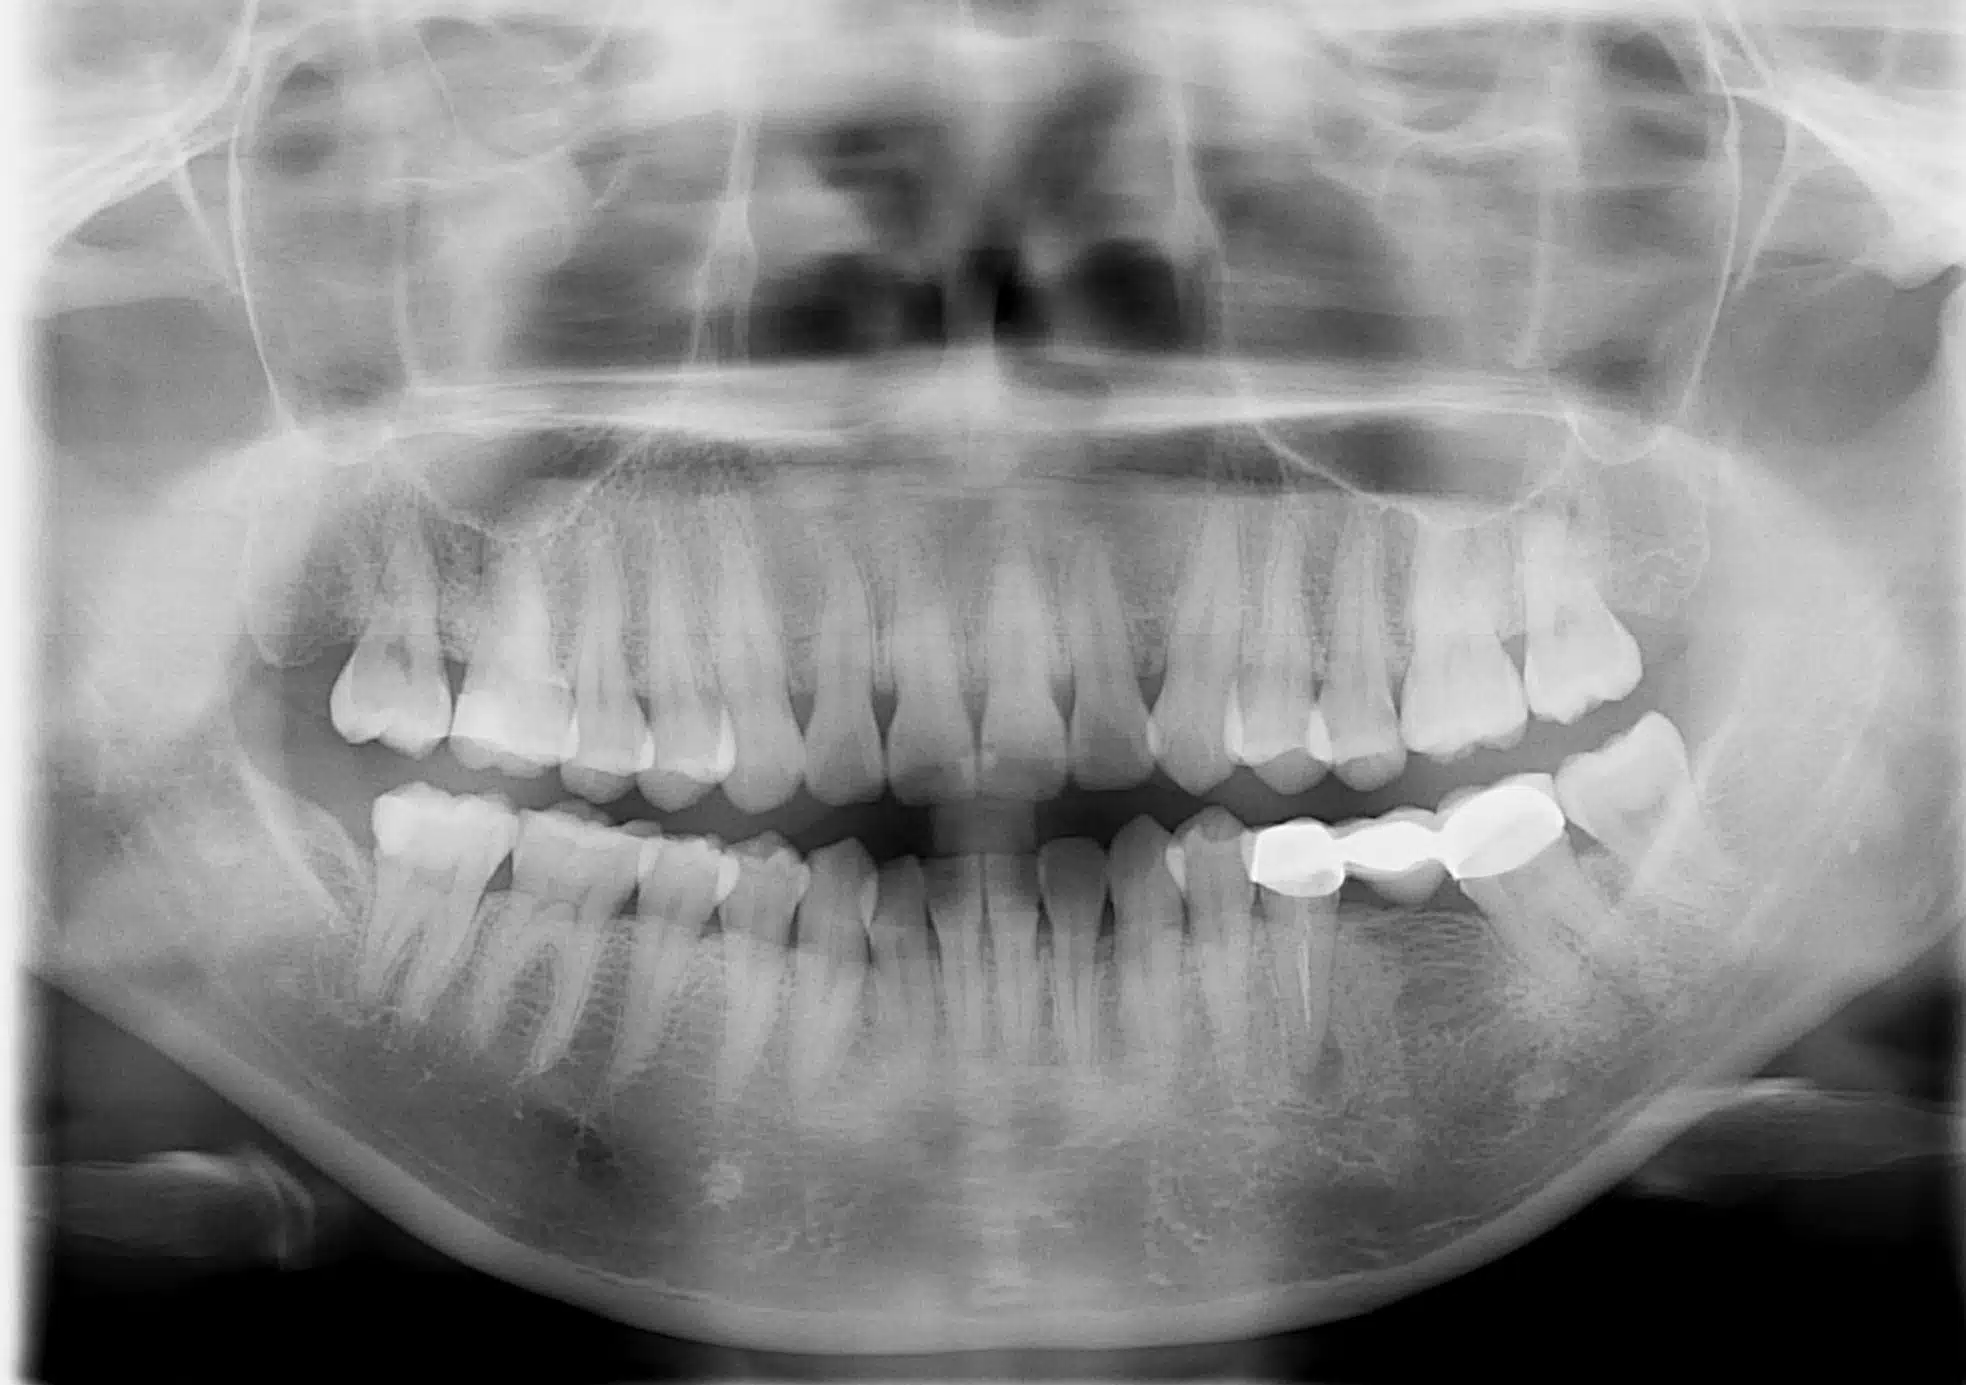

2. Types of Dental X-Rays: a. Bitewing X-Rays: These X-rays focus on the upper and lower back teeth, revealing decay between teeth, bone loss, and the fit of dental restorations. b. Periapical X-Rays: These X-rays provide detailed images of the entire tooth, including the root and surrounding bone. They help identify abscesses, root infections, and bone abnormalities. c. Panoramic X-Rays: These X-rays capture a broad view of the entire mouth, including all teeth, upper and lower jaws, sinuses, and temporomandibular joints. They help diagnose impacted teeth, fractures, tumors, and evaluate overall dental development. d. Cone Beam Computed Tomography (CBCT): This advanced 3D imaging technique provides highly detailed images of the teeth, bone, nerves, and soft tissues. CBCT is commonly used in complex cases such as dental implants, orthodontic treatment planning, and oral surgery.